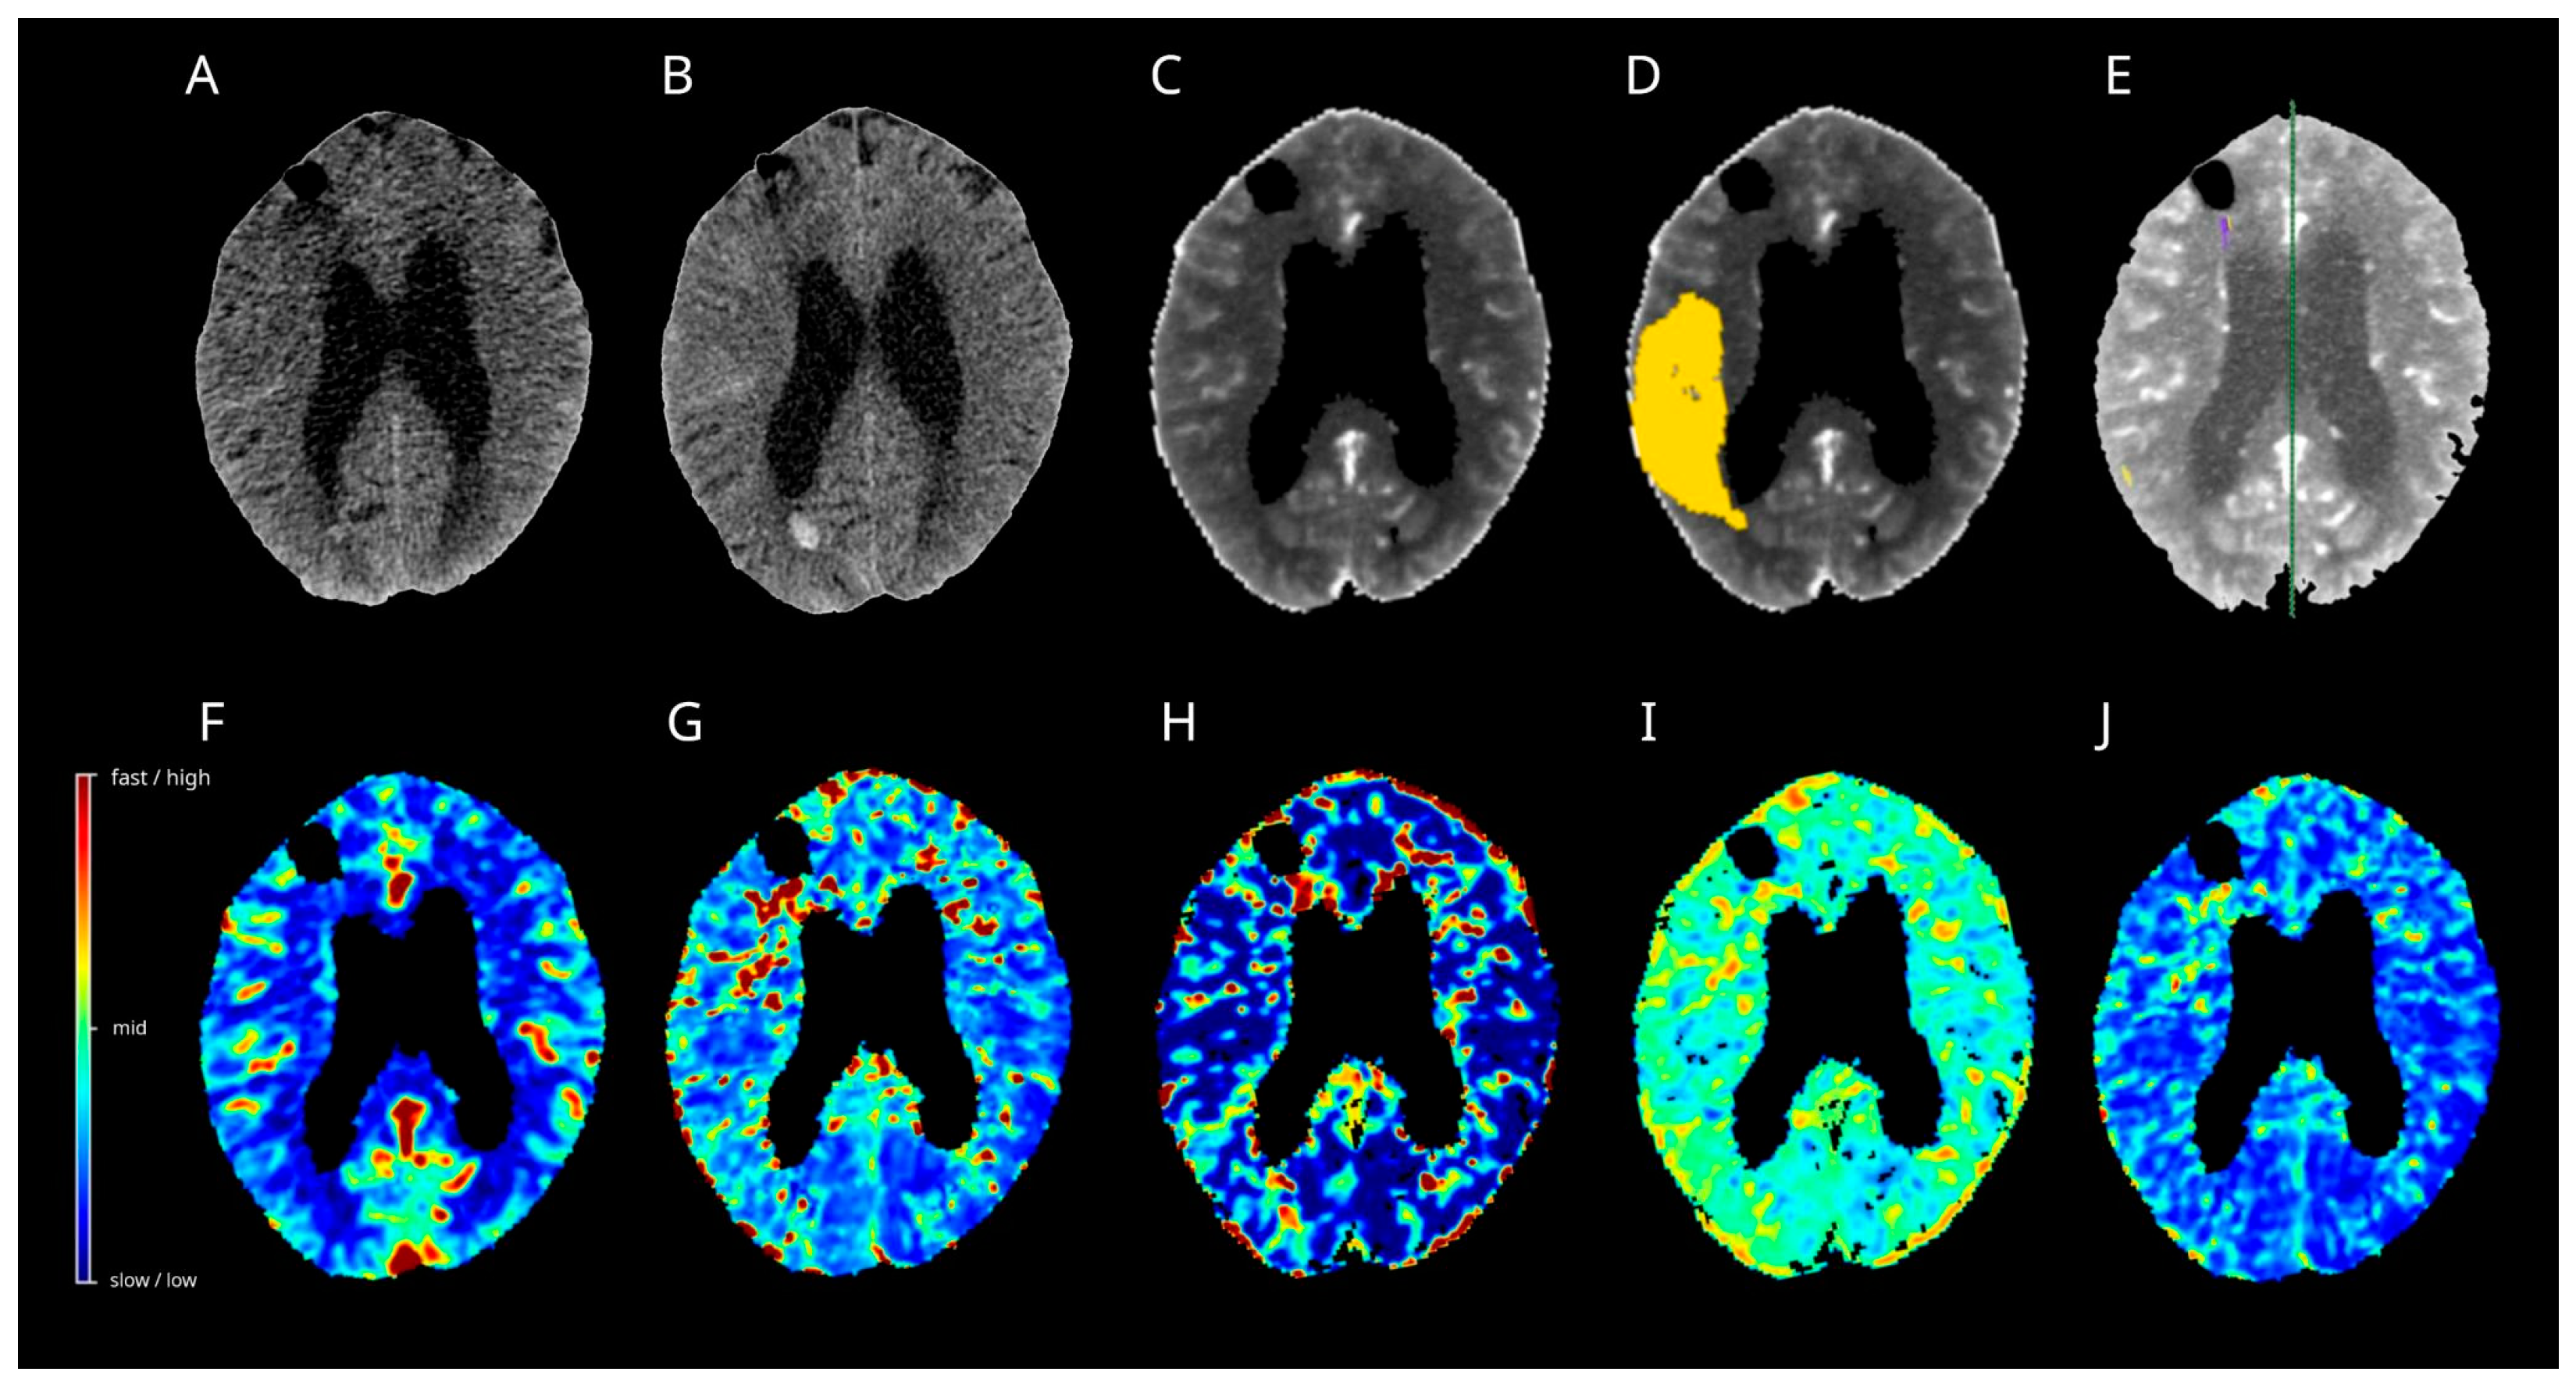

3.10. Case 1

3.11. Case 2